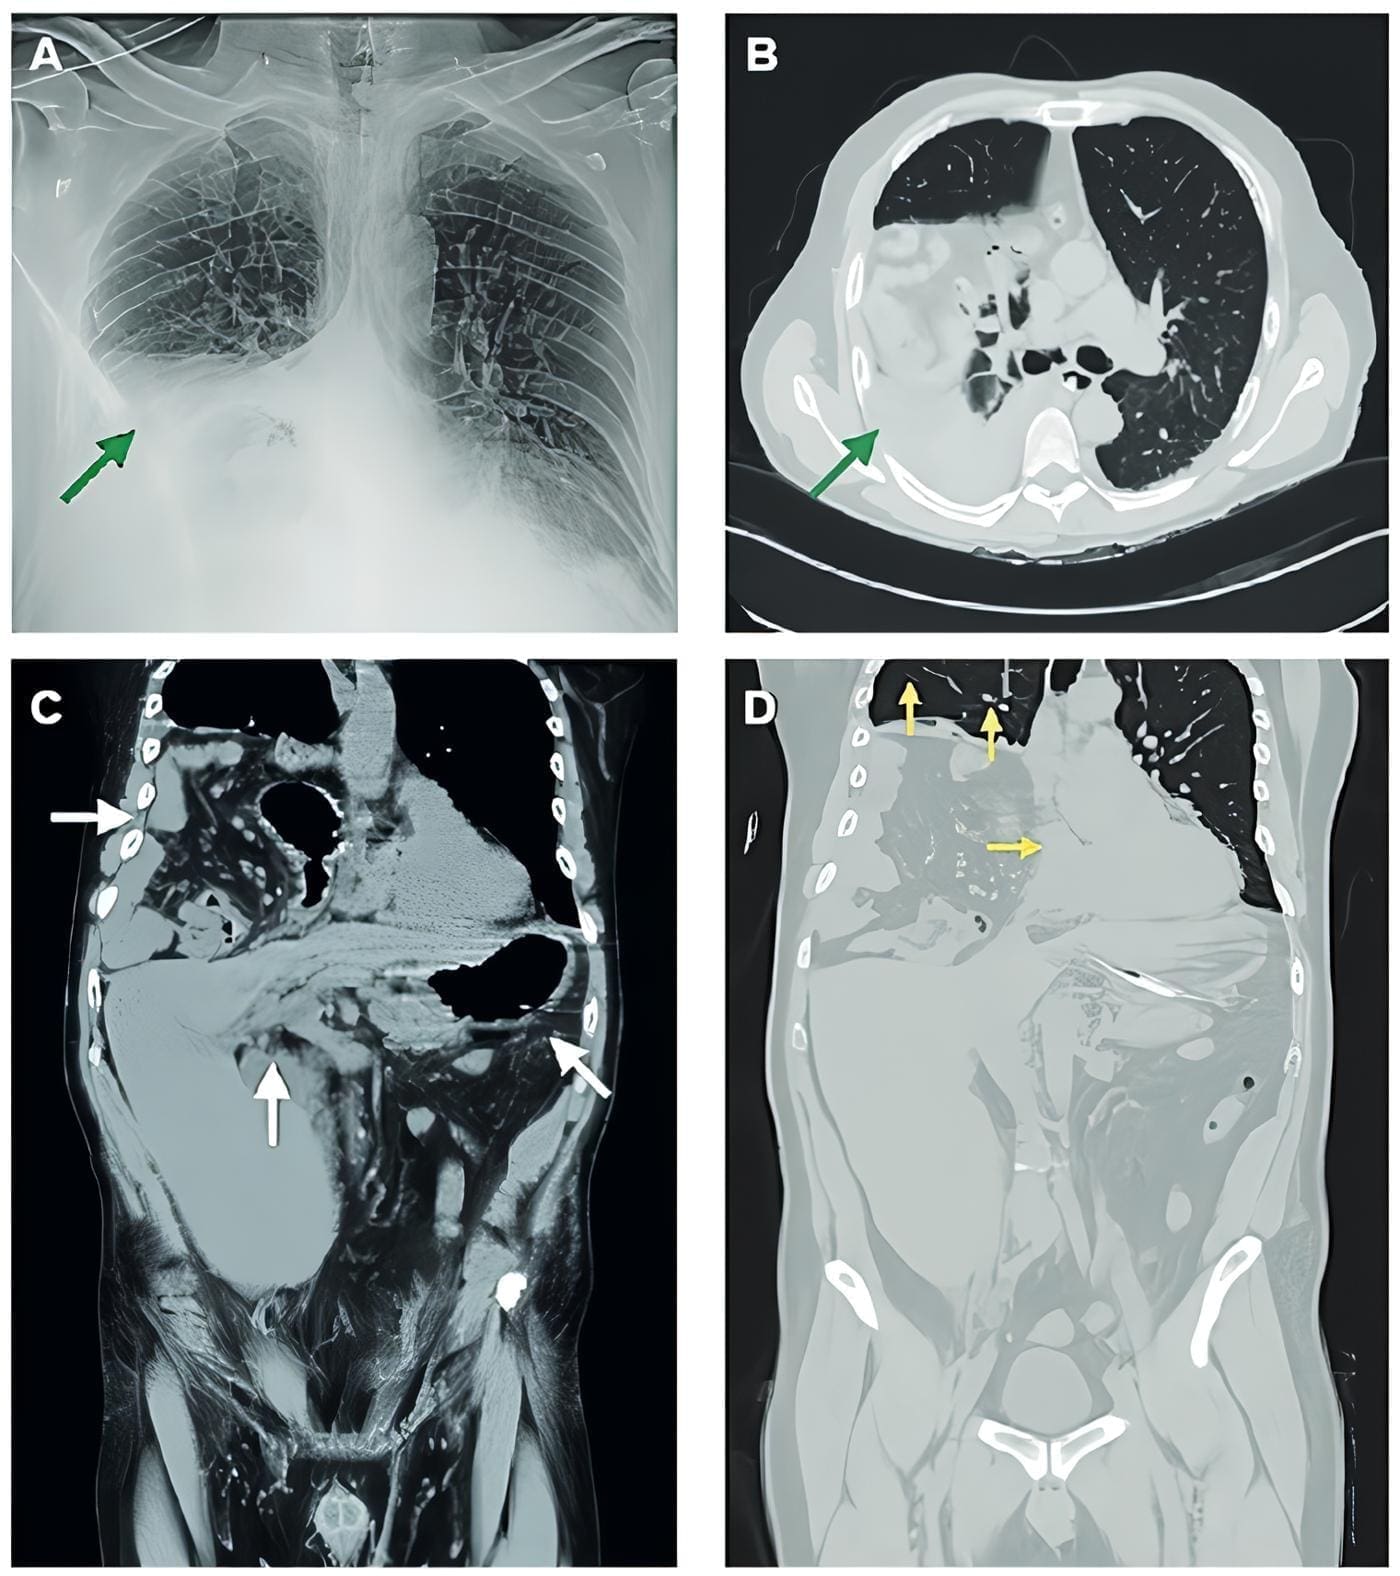

Se realizó una tomografía tóraco abdominal la cual demostró la presencia de hernia hiatal mixta y vólvulo gástrico; en el parénquima pulmonar no se observaron cambios sugestivos de neumonía por SARS-CoV-2 (Figura 1).

Figura 1: A) Radiografía posteroanterior con opacidad en hemitórax derecho. B) Tomografía de tórax en plano axial que revela estómago, intestino delgado, colon y mesenterio en situación intratorácica derecha; no se observan cambios en parénquima pulmonar compatibles con neumonía viral. C) Tomografía tóraco-abdominal (plano coronal) que demuestra hernia hiatal con hemidiafragma derecho de situación alta y vólvulo gástrico. D) Tomografía en plano coronal que muestra restricción mecánica del pulmón derecho con desplazamiento contralateral de estructuras mediastinales. Imagen original, fuente: los autores.ADADCB